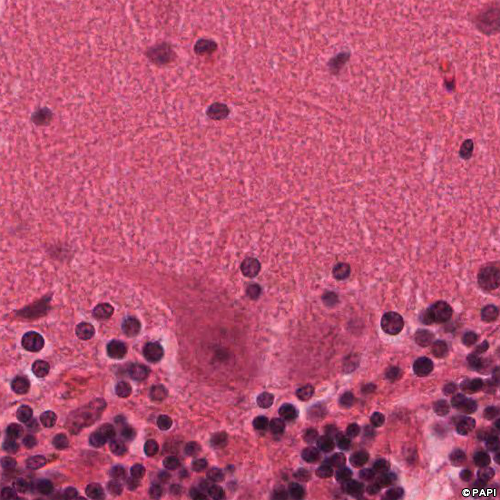

Yellow arrows indicate the Purkinje cells. Blue ones indicate the nuclei of the Bergmann glia, which is the astrocyte in the Purkinje cell layer. A white arrow points the basket cell in the molecular layer.